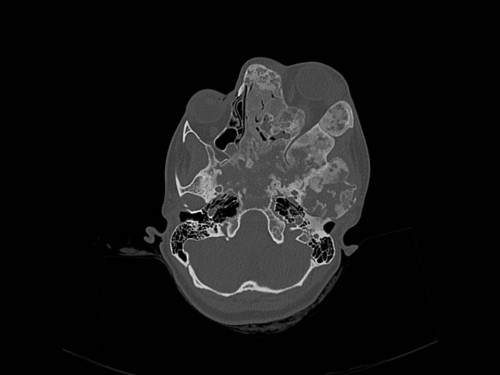

Knochendeformitäten seit der Geburt

Fall-ID: 712

ICD: M85.09

Autor*in: Sandra Klipp

Eine 16-jährige Patientin kommt in eine MKG-chirurgische Praxis zur Abklärung der weiteren Vorgehensweise bzgl. ihrer Erkrankung.

Sie betrachten die angefertigten Röntgenbilder. Welche der folgenden Röntgenbefunde ist korrekt? Ossäre Auftreibungen im Bereich …

- A… der Mandibula links.

- B… des Os frontale links.

- C… des Os zygomaticum links.

- D… des Os temporale links.

- EAlle genannten Aussagen sind korrekt.

Bildgebung - OPAN 2004